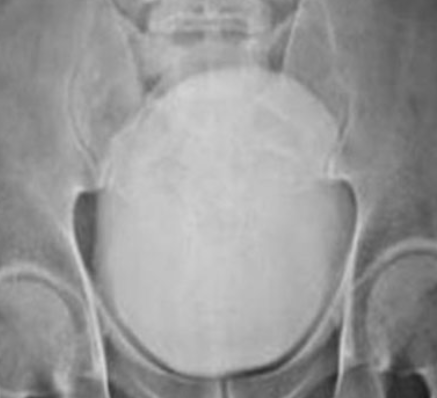

Αξονική τομογραφία οπισθοπεριτοναίου. Κίτρινα βέλη – Αμφοτερόπλευρη διάταση ουρητήρων. Ευγενική παραχώρηση Dr. V. Penopoulos.